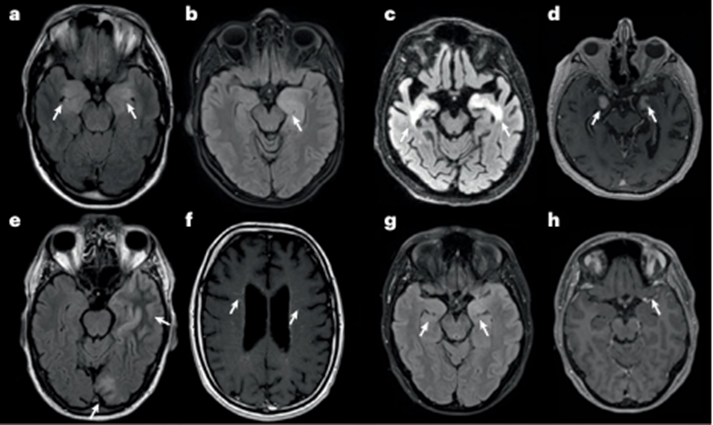

神经影像学(脑 MRI)

脑 MRI 可显示边缘性脑炎的特异性表现

图 4 自身免疫性脑炎患者的典型 MRI 表现

a 最典型的 MRI 模式为双侧内侧颞叶在 T2 / FLAIR序列上呈高信号(箭头),即边缘性脑炎。

b 较少见的表现为单侧内侧颞叶在 T2/FLAIR 序列上呈高信号(箭头)。

c 该 T2/FLAIR 图像初看可见典型高信号(箭头),但病变范围略超出内侧颞叶区域。

d 该 T1 序列上的强化表现(箭头)为 “警示信号”;该患者最终确诊为Whipple。

e 抗 GABAA 受体脑炎中,FLAIR 序列可见多灶性、边界不清的大片白质病变(箭头)。

f 抗 GFAP 星形细胞病的典型 MRI 特征为增强上呈线性 / 放射状血管周围强化(箭头)。

g 最后一例患者的 T2/FLAIR 图像符合自身免疫性脑炎典型表现,显示双侧高信号(左侧较右侧明显;箭头)。

h 钆强化表现(箭头)不典型(警示信号);该患者最终确诊为多形性胶质母细胞瘤。

纵向 MRI 随访具有重要临床价值:可确认治疗反应、观察既往 T2/FLAIR 病变的消退情况、监测提示不良临床结局的脑萎缩进展,以及发现复发或新发脑病变。